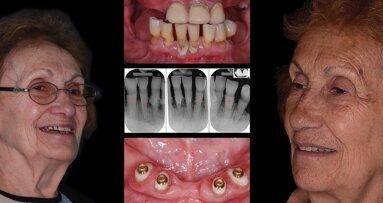

Los autores describen el procedimiento más sencillo, económico y funcional para la rehabilitación del paciente edéntulo total, por medio de la ...